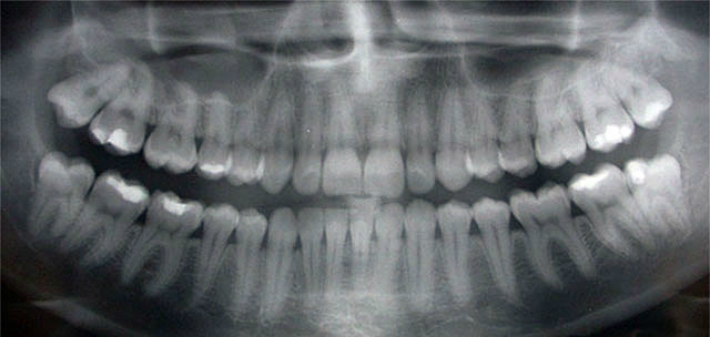

It is true: new technology in the form of digital X-rays expose patients to less radiation than the amount expected from a traditional dental X-ray. Digital X-rays reduce radiation exposure by up to 80%, meaning that they expose you to even less than 1 mrem to minimize your risk of developing cancer.

Because using the latest technology improves the quality of our patient care, Arkansas Family Dental uses digital X-rays to monitor the development of your family’s teeth. If you are interested in digital X-rays, make an appointment with Arkansas Family Dental or call us at 501-683-8886 to learn more.